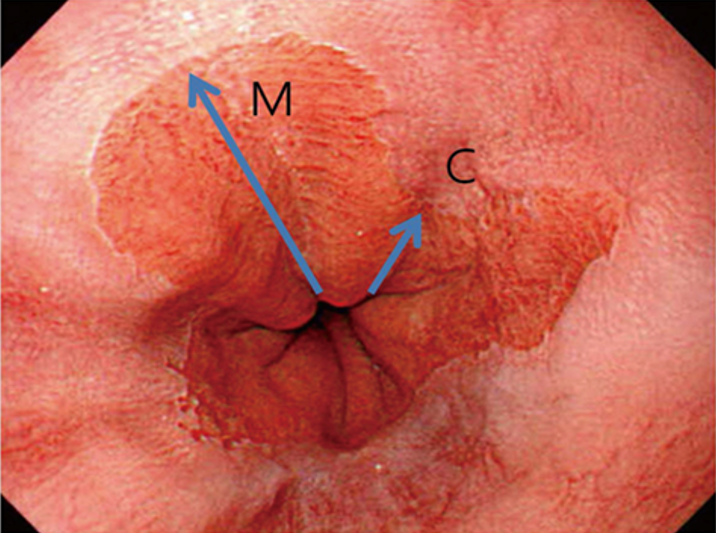

Ved bekreftet høygradig dysplasi (HGD, Tis) –og/eller adenokarsinom, T1a, skal pasienten tilbys endoskopisk behandling. Dette innebærer reseksjon av lokaliserte forandringer (EMR) kombinert med RFA av resterende BØ. Endoskopisk submukosal disseksjon (ESD) har ikke vist seg å gi bedre resultater enn EMR, som er en enklere og tidsmessig raskere teknikk (Komeda, Bruno, & Koch, 2014; Terheggen et al., 2017). «Multiband mucosectomy» eller gummibånd EMR er den enkleste og foretrukne metode. Ved T1b kan EMR også være aktuelt om pasienten er «borderline fit» for kirurgi, forutsatt fravær av lymfeknuter og en begrenset submukosal innvekst (<500 µm). Dette er pasienter som må diskuteres nøye i MDT møter for spiserørskreft.

Høygradig dysplasi uten synlige lesjoner er sjelden, og utgjør færre enn 20% av pasientene med HGD. Fravær av synlige lesjoner hos en pasient med HGD, kan være en oversett lesjon, eller over-staging av histologien (66). Om pasienten ikke allerede er i et pakkeforløp, er start pakkeforløp aktuelt ved HGD.

Ved lesjoner over 15 mm, manglende løft og usikkerhet om innvekst i submukosa, vil om ikke kirurgi er aktuelt, ESD i erfarende hender være bedre enn EMR (Malik, Sharma, Sanaka, & Thota, 2018).